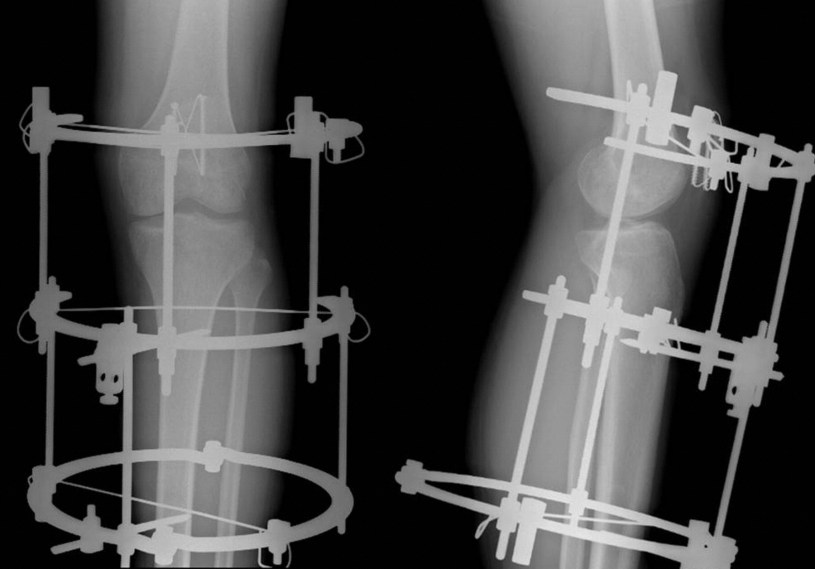

Gli interventi con tecnica Ilizarov consistono nel fissaggio di una struttura metallica attorno agli arti tramite fili e chiodi che attraversano le ossa. Dopo l’installazione sono eseguite microfratture chirurgiche nell’osso. Ogni giorno è il paziente stesso a manovrare il fissatore esterno accrescendo la distanza tra le parti fratturate di un millimetro al giorno così da stimolare l’osso alla naturale calcificazione e quindi all’allungamento. Insieme alla crescita dell’osso si allungano naturalmente anche le altre strutture contenute nell’arto: vasi, muscoli, tendini e nervi.